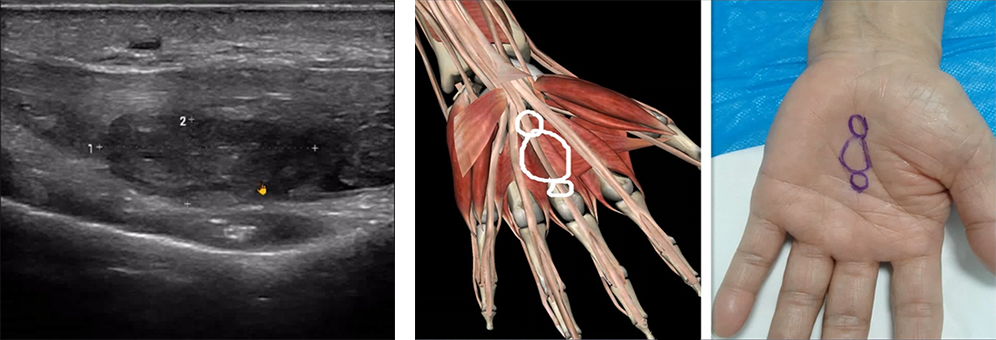

Post-surgery, the patient reported thumb pain, movement restriction, and numbness in the hand.

The ultrasound revealed carpal tunnel syndrome with synovial cysts compressing the recurrent motor branch of the median nerve.

For medical professionals looking to buy a handheld ultrasound machine, this case highlights the machine' s ability to detect subtle post-surgical complications that could otherwise be missed.